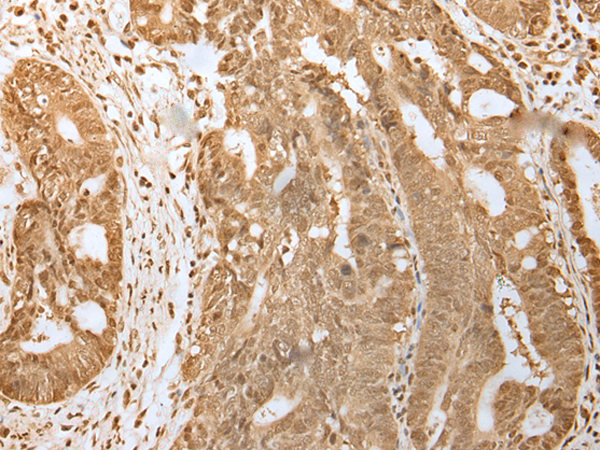

ELISA, IHC |

IHC positive control: |

Human gastric cancer and Human tonsil |

IHC Recommend dilution: |

25-100 |